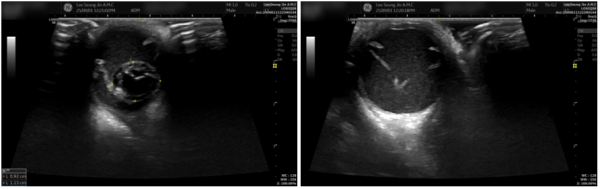

안구 초음파 검사

cc52a523279e78f86d81b8f95c4a3e80_1767160157_6638.png

초음파에서는 수정체가 뒤쪽으로 탈구된 상태가 확인되었습니다.

주변에는 출혈과 염증 산물이 보였고,

이미 망막박리가 진행되어 시력 회복이 어려운 단계였습니다.

안구가 비대해지고 시신경 압박이 심해

상당한 통증이 있었을 것으로 판단되었습니다.